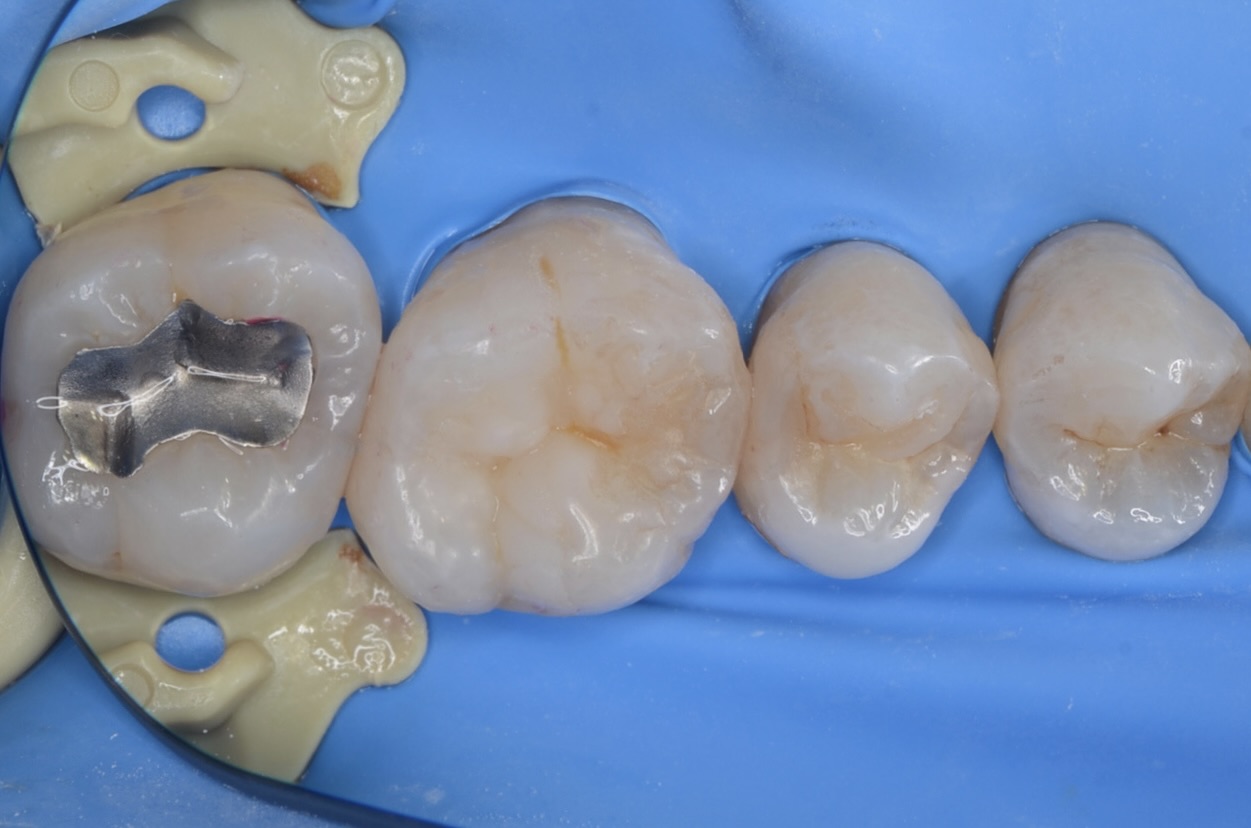

充填終了

わざと歯と歯の間の隙間を残します。 -

1週間後

歯と歯の間の隙間は閉じています。フロスを入れてみて歯間のキツさを確認しました。問題ありませんでした。 -